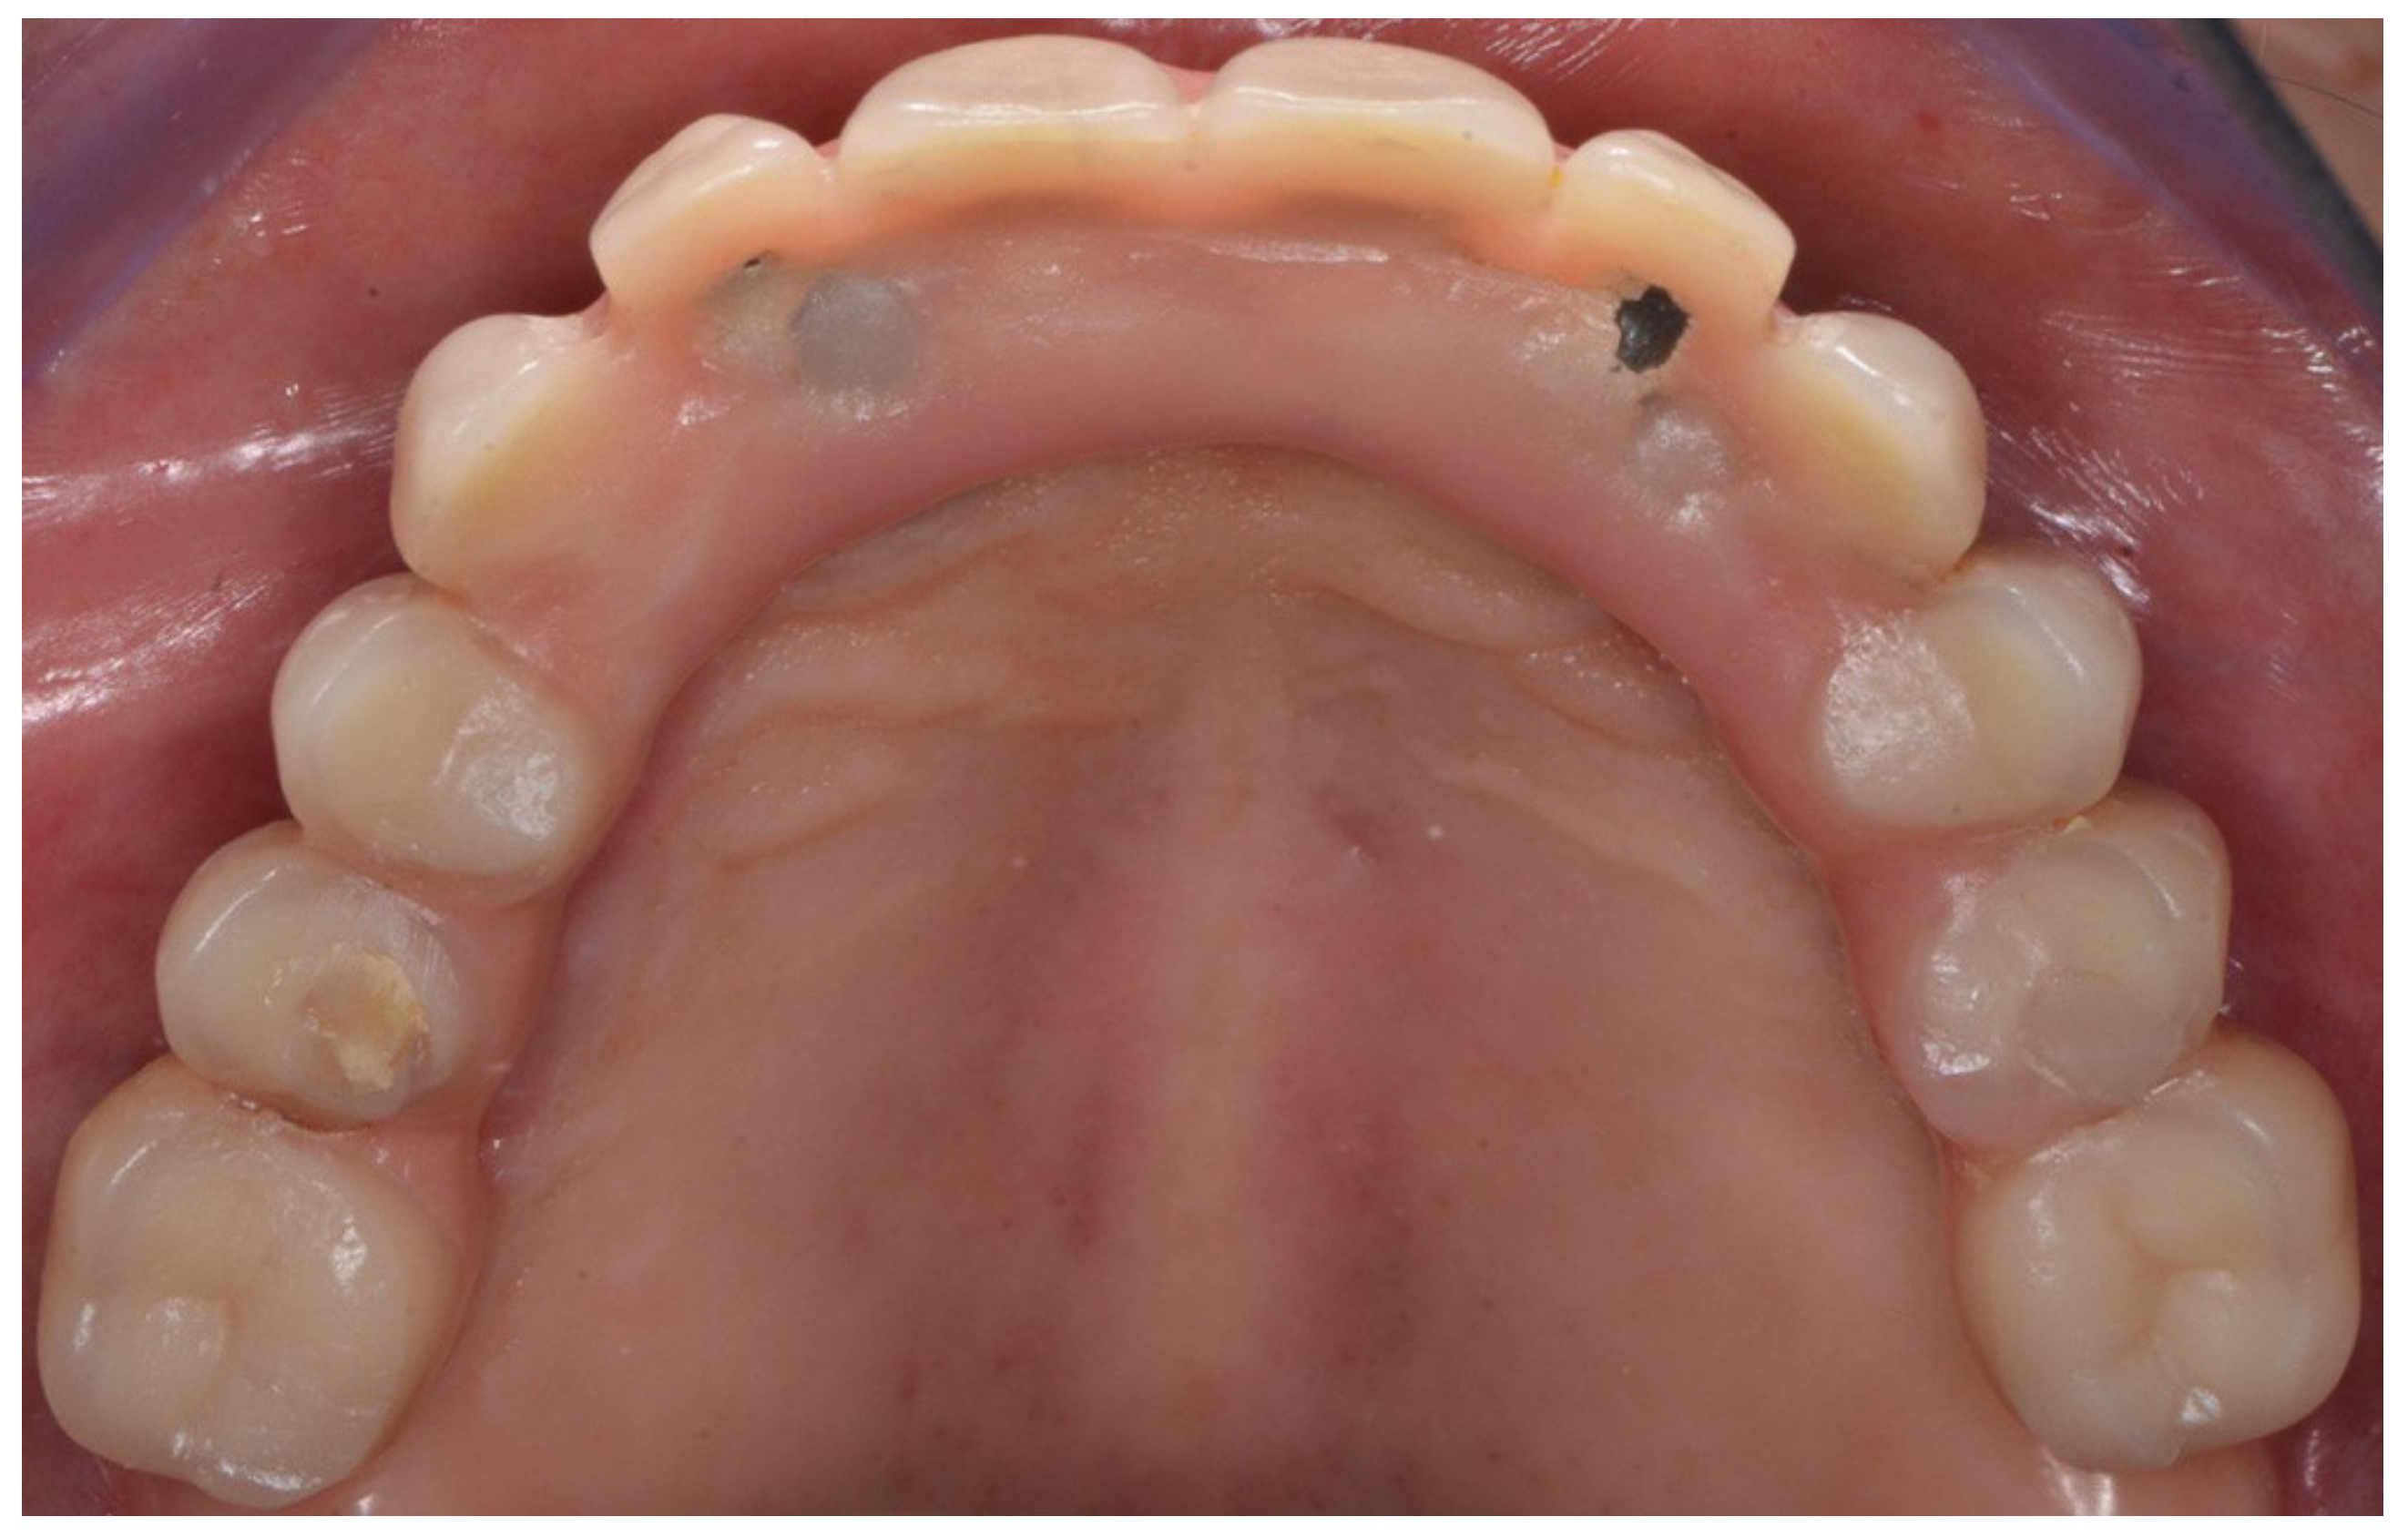

Figure 6.

Definitive prosthesis with cantilevers after 7 years of use.

Figure 7.

Occlusal view of definitive prosthesis after 7 years of use.